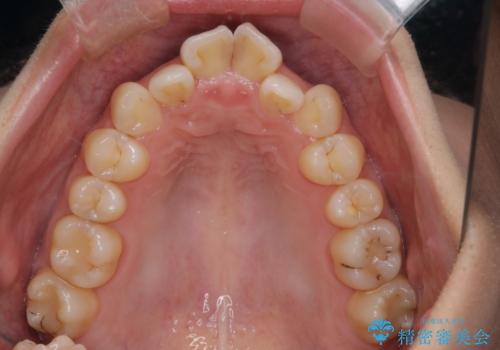

- 前歯のがたつきを治したいという主訴で来院されました。1年後に転勤の可能性があり短期間での治療を希望されました。今回は非抜歯の治療を計画し、IPRと拡大をし、前歯の叢生を改善しました。

前歯のがたつきを治しながら2番の反対咬合も改善させました。短期間で終了し満足していただけました。